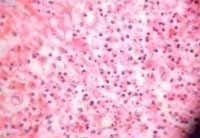

Los cultivos pre e intraquirúrgicos reportaron negatividad para anaerobios y positividad para Klebsiella pneumoniae y Acinetobacter baumanii sensibles a los antibióticos usados en el momento. La histopatología reveló-necrosis colicuativa tanto en piel como en tejidos subcutáneos además de infiltrado polimorfonuclear (Figura 4).

Fig. 4 Histopatología correspondiente al presente caso. Muestra necrosis colicuativa, innfiltrado polimorfonuclear y microtrombos en tejidos subcutáneos.

Aunque la histopatología no es el pilar diagnóstico de esta enfermedad, es importante anotar que generalmente se encuentra disolución de la dermis papilar en la fase temprana, el cuadro luego progresa hacia necrosis de la epidermis, dermis y grasa subcutánea con infiltración de leucocitos polimorfonucleares (5), como observamos en el caso que presentamos. También se ha reportado que el tejido macroscópicamente sano en la periferia de la lesión presenta generalmente evidencia histológica de necrosis (16), por esta razón, es importante como lo ilustra el presente caso, realizar un desbridamiento que sobrepase el límite macroscópico de necrosis en los tejidos profundos comprometidos.